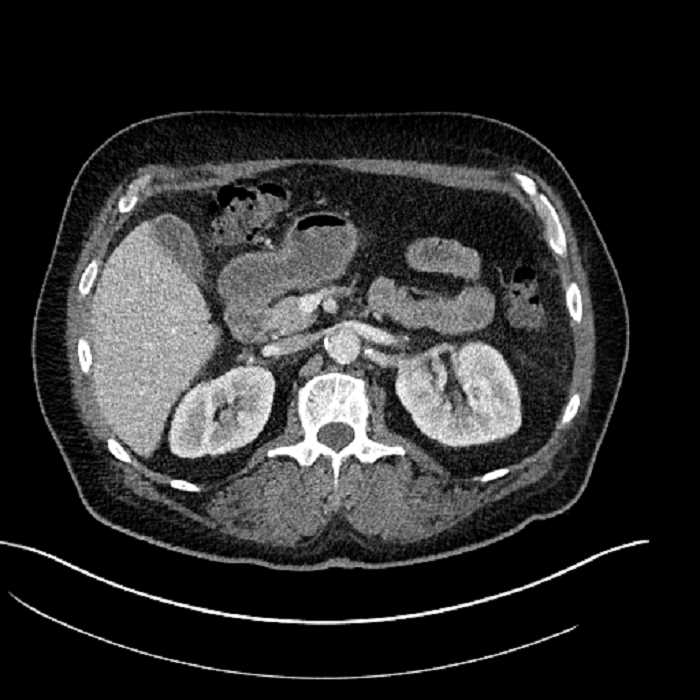

• Large fluid density structure in hepatic segments 7 and 8 measuring 10 x 7 x 7 cm with internal septation and circumferential ill-defined low density compatible with edema

• Peripherally enhancing subcapsular collections along the anterior margin of the left hepatic lobe measuring 3 x 1 cm and 2 x 1 cm

• Clearly marginated fluid density structure in segment 7 and several other scattered tiny hypodensities, which likely represent cysts

• Hepatic abscess

Acute sigmoid diverticulitis complicated by a small contained perforation and a large abscess in the right hepatic lobe. Additional small subcapsular abscesses along the anterior margin of the left hepatic lobe.

• The classic CT imaging appearance is a double target sign with internal low density surrounded by an internal enhancing rim (capsule) and a low density external rim (edema)

• Abscesses may be unilocular or multilocular

• Gas is present in a minority of cases

Hepatic abscess showing the double target sign with low density internally surrounded by a thin inner enhancing rim (red arrow) and ill-defined outer low density rim (yellow arrow). Blue arrow indicates an internal septation. Red arrows: additional smaller subcapsular abscesses. Red arrow: focal contained perforation associated with diverticulitis.